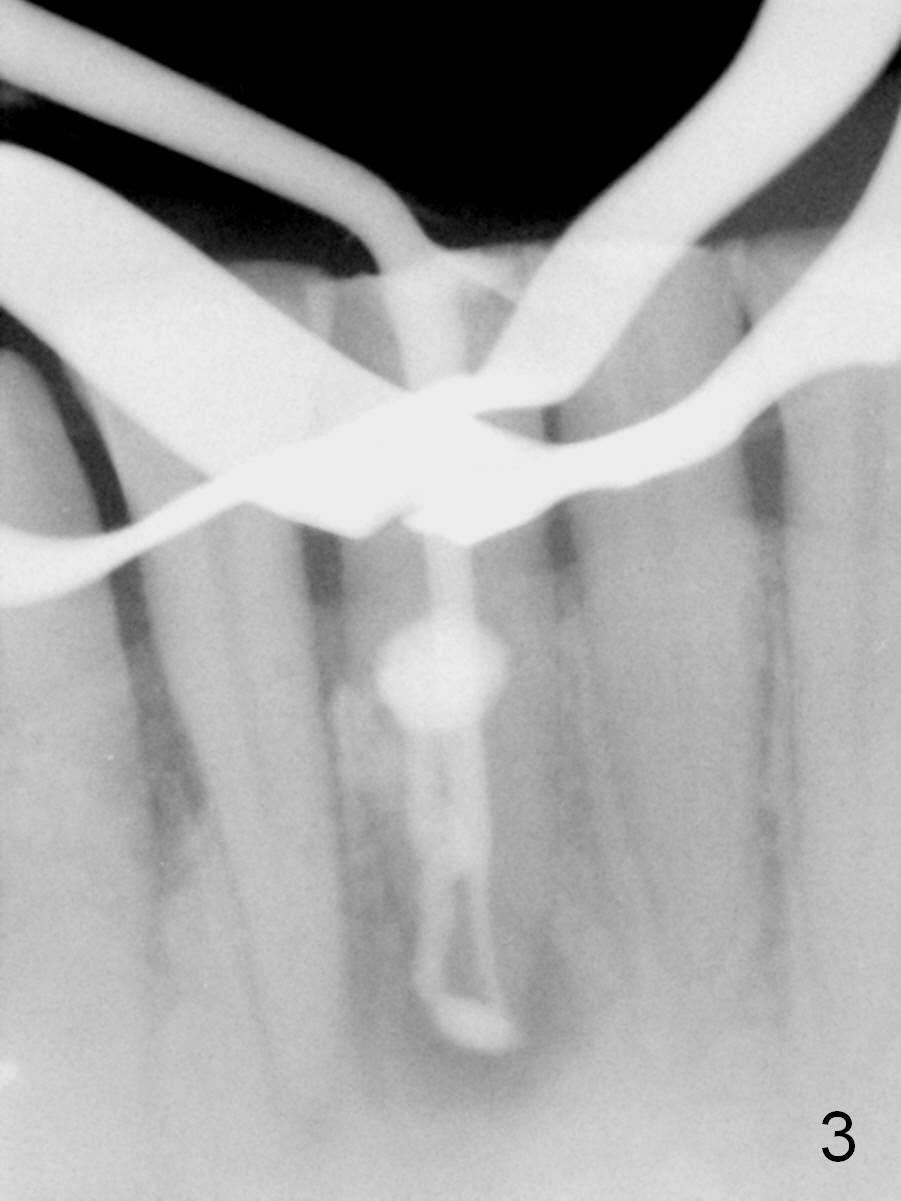

A 45-year-old man has had a chronic fistula associated with the tooth #25 (Fig.1). There is purulent discharge sometimes. After debridement with hand files #10-20 and rotary one 30/06, a master cone 30/.06 is inserted incompletely (Fig.2). After rotary files 30/.08 at 16.0 mm and 30/.10 at 15.0 mm and hand files 10-20 at 17 mm, the master cone is apparently inserted to the WL. With application of Endo Sequence Sealer (syringe), the master cone is reinserted (Fig.3). When the rubber dam is removed, the sealer is found to have expelled from the fistula. With an endo curette (Fig.5), the sealer is removed from the deepest portion of the sinus tract (apex of the tooth). What do you want to know the outcome of the supplementary surgical maneuver? The sealer is gone (Fig.6). The immediately supplementary treatment avoids a separate apicoectomy. No fistula is noted <2 weeks postop (Fig.7). The attrition is due to #8 and 9 veneers, fabricated 8 years earlier. The tooth #24 is symptomatic with loss of incisal composite nearly 4 years postop (Fig.8 <). After 30/.04 gutta percha (GP) try in (Fig.9), RCT is finished without accessory GP (Fig.10).